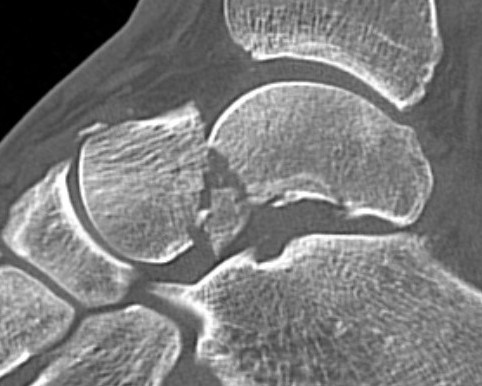

Xray / CT

Ensure no displacement / malalignment

Canale view

- evaluates talar neck

- foot everted 15 deg

- look for medial shortening / varus

Xrays

| AP | Lateral | Canale View |

|---|---|---|

| Entry point of the screws |

Evaluate neck reduction

|

Evaluates the neck reduction |

Lateral off articular surface Medial through articular cartilage |

Depth of screws |

Beam angled 75o to foot Foot 15o pronated |